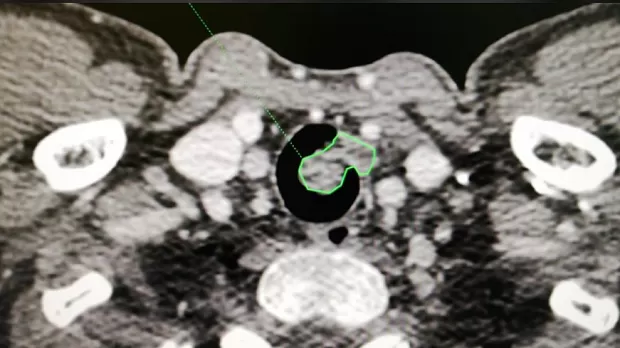

Пациент Р. 1988 г.р., госпитализирован в клинику для дообследования и оперативного лечения с диагнозом: образование в/3 трахеи. На амбулаторном этапе при бронхоскопии выявлено образование в/3 трахеи, биопсия не взята. После госпитализации в нашу клинику проведено КТ, на томографии имеется образование размерами 2.4х2.3 см, с ножкой 13 мм, с плотностью до 40 ед, имеется инвазия в области ножки в подслизистый слой на 6 мм, рядом увеличенный лимфоузел.